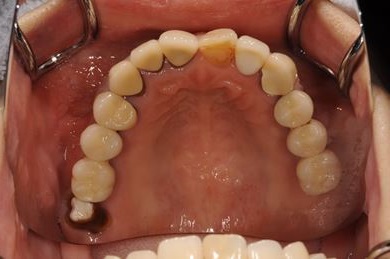

骨再生スピードインプラント治療+セラミック治療

| 主訴 | 左上の歯に以前から歯周病があり、多少のぐらつきがあったが、ここにきていよいよ限界になりました。食事に影響があるので、インプラントを視野に、とりあえずは抜歯をと思っています。 | ||||||||||||||||||||||||||||||||

| 治療方針 | サイナスリフトにて上顎洞を拳上し、インプラント治療を可能にする。抜歯と同時にインプラント埋入を行い、治療期間を短縮する。 | ||||||||||||||||||||||||||||||||

| 治療内容 | インプラント9本(抜歯即日スピードインプラント、サイナスリフト)、ハイブリッドセラミッククラウン12本(ハイブリッドセラミック用土台3本) | ||||||||||||||||||||||||||||||||

| 総治療費 | 4,157,213円 | ||||||||||||||||||||||||||||||||

| 治療期間 | 1年0ヶ月 |